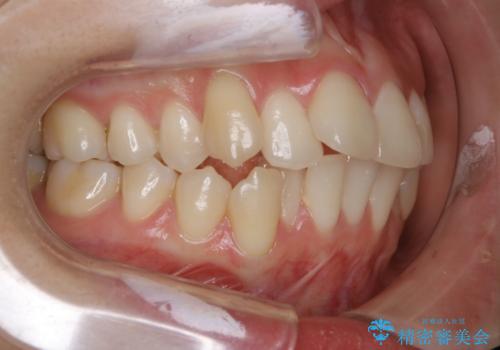

- 前歯のガタつきと噛み合わせの改善を主訴に初診来院され、審査の結果マウスピース装置による非抜歯での矯正を行うこととなりました。

元々の顎骨や口腔・歯槽骨が小さく、どうしても歯が並びきらない状況になっていました。マイクロインプラントという固定源からゴムかけを行うなど、補助装置を活用しながら臼歯部を順番に遠心方向(奥)に移動させていくことで抜歯をしなくても歯が並ぶよう計画を立てました。

歯を並べるスペースを作るために、歯の遠心移動と歯列の拡大、歯自体を少しだけ小さく削る(IPR)という方法を複合的に組み合わせて配列を行いました。遠心移動用のゴムかけにはマイクロインプラントという小さいネジを用いて骨に直接固定源を求めました。